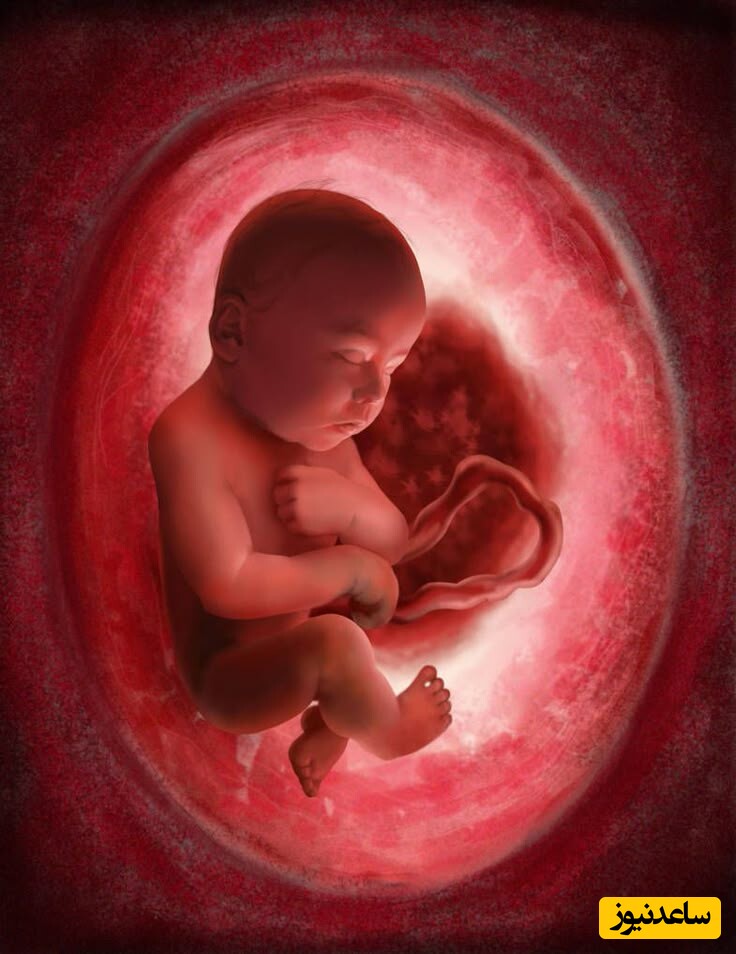

صدک رشد جنین چیست و چقدر باید باشد؟ راهنمای کامل برای مادران باردار

صدک رشد جنین چیست؟

صدک رشد جنین، معیاری است که اندازهگیریهای جنین مانند وزن، طول، دور سر و دور شکم را با دادههای استاندارد جنینهای همسن مقایسه میکند. این معیار معمولاً در سونوگرافیهای دوران بارداری بررسی میشود و به صورت درصدی بیان میگردد. برای مثال:

صدک رشد جنین چقدر باید باشد؟

به طور کلی، صدک 50 نشاندهنده میانگین رشد طبیعی است، اما محدوده 10 تا 90 نیز معمولاً طبیعی تلقی میشود. با این حال: